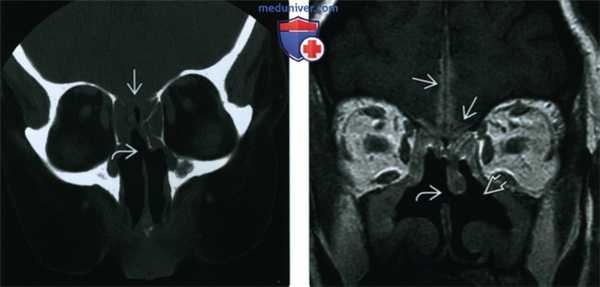

(Слева) При корональной КТ у пациента с ГПА, хроническим риносинуситом и жалобами на головную боль определяется перфорация носовой перегородки, а также сливное снижение пневматизации решетчатых пазух с обеих сторон в сочетании с деструкцией решетчатой пластинки.

(Справа) При корональной МРТ у этого же пациента определяется диффузное утолщение слизистой оболочки верхнечелюстных и решетчатых пазух, перфорация носовой перегородки, двухсторонняя деструкция носовых раковин и наружных стенок носовой полости. Обратите внимание на контактный лахименингит передней черепной ямки.

4. Рекомендации по визуализации:

• Лучший метод диагностики:

о «Костная» корональная КТ пазух для первоначальной оценки

- Аксиальная МСКТ с реформатированием также хорошо подходит для обнаружения эрозий костей

• Выбор протокола:

о При поражении орбиты, глубоких тканей лица, основания черепа, оболочек мозга, заподозренном на КТ или клинически

- МРТ С+ FS